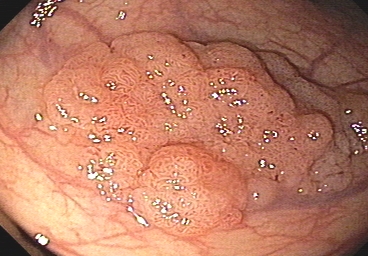

This tool is designed to assist in the detection, segmentation, and classification of colon polyps by processing medical images and providing AI-powered insights.

Colon Polyp Analysis Tool

Uploaded Image

Analysis Results